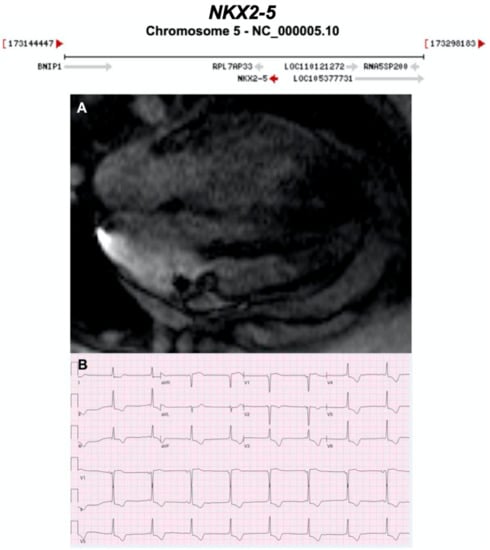

3.2.15. NK2 Homeobox 5 (NKX2-5) (Encoded by NKX2-5)

- Yuan, F.; Qiu, X.B.; Li, R.G.; Qu, X.K.; Wang, J.; Xu, Y.J.; Liu, X.; Fang, W.Y.; Yang, Y.Q.; Liao, D.N. A novel NKX2-5 loss-of-function mutation predisposes to familial dilated cardiomyopathy and arrhythmias. Int. J. Mol. Med. 2015, 35, 478–486. [Google Scholar] [CrossRef] [PubMed]

- Perera, J.L.; Johnson, N.M.; Judge, D.P.; Crosson, J.E. Novel and highly lethal NKX2.5 missense mutation in a family with sudden death and ventricular arrhythmia. Pediatric Cardiol. 2014, 35, 1206–1212. [Google Scholar] [CrossRef] [PubMed]

- Sveinbjornsson, G.; Olafsdottir, E.F.; Thorolfsdottir, R.B.; Davidsson, O.B.; Helgadottir, A.; Jonasdottir, A.; Jonasdottir, A.; Bjornsson, E.; Jensson, B.O.; Arnadottir, G.A.; et al. Variants in NKX2-5 and FLNC cause dilated cardiomyopathy and sudden cardiac death. Circ. Genom. Precis. Med. 2018, 11, e002151. [Google Scholar] [CrossRef]